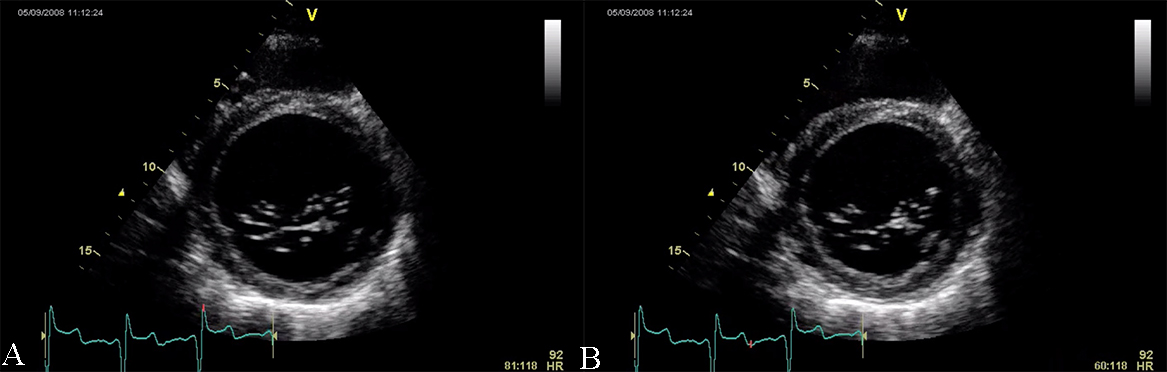

Restrictive cardiomyopathy (RCM) is characterized by non-dilated ventricles, mild or no myocardial hypertrophy with impaired ventricular filling, thus it is defined by abnormal ventricular diastolic function with a normal size LV (see Fig. 8). In the early stages of the disease, the systolic function of the LV is also normal [38].

Fig. 8.The echocardiographic aspect of RCM in an elderly patient presenting with signs and symptoms of heart failure. Apical 4 chamber view showing severe biatrial enlargement, with left atrial thrombus and non-dilated left and right ventricles.

The causes of RCM can be classified as non-infiltrative (familial) or infiltrative (storage diseases), but the same pattern can be found in other disorders like diabetic cardiomyopathy, scleroderma, and endomyocardial fibrosis [38, 39, 40]. An accurate myocardial investigation by MRI and myocardial scintigraphy allows the diagnosis of different types of myocardial amyloidosis which is increasingly observed in the elderly either by transthyretin (aTTR) or by AL–light immunoglobulin chains in different plasmacytomas [41]. Another type of RCM is found in sarcoidosis and it can cause global or regional LV wall motion abnormalities. In some cases, the changes are specifically revealed on the basal posterior and lateral wall of the LV [42, 43, 44]. The most common finding is myocardial thinning, but RCM can also present with hypertrophy or it can include myocardial aneurysms [38, 45, 46, 47]. In some RCMs such as endomyocardial fibrosis or hypereosinophilic syndrome apical intraventricular thrombosis may be recognized; this may be responsible for pulmonary or systemic cardioembolism [48]. In RCM due to amyloidosis, apart from hypertrophy and wall motion abnormalities (Fig. 9), valvular involvement may also be noted with thickened aortic cusps or mitral leaflets determined by local deposition of amyloid [49].

2D echocardiography, as mentioned before, highlights a low or normal diastolic volume of the LV associated with normal or only mildly reduced LV ejection fraction, as criteria for RCM. Also, one or both atrial enlargement is identified, with increased pressures, and normal pericardium. Once the typical pattern of RCM is identified, the echocardiogram can reveal also some features for a specific etiology. For example, in cardiac amyloidosis, the left and right ventricular walls are often mildly and symmetrically thickened, the myocardium may have a granular appearance, and myocardial strain imaging may show preserved apical function. However, it is not sufficient information neither to confirm, nor exclude cardiac amyloidosis [39, 40, 50], and further testing is needed. Moreover, in sarcoidosis global or regional (typically basal posterior and lateral) LV wall motion abnormalities may be observed. The most common finding is myocardial thinning, while less common findings include myocardial aneurysms, hypertrophy, and pericardial effusion [51, 52]. In eosinophilic inflammation of the myocardium or hypereosinophilic syndrome, the echocardiogram is often unrevealing during the initial necrotic stage. In the thrombotic stage of the disease, the damaged endocardium may have associated thrombus, predominantly involving the ventricular apex [3, 5, 38, 52, 53]. During the last, fibrotic stage, increased endomyocardial echogenicity is seen, affecting one or both ventricles, sometimes with overlying thrombus; the ventricular filling can be restricted, and atrioventricular valve leaflets may be tethered [53, 54, 55]. A pattern similar to hypereosinophilic syndrome can emerge in endomyocardial fibrosis. It may be characterized by LV, RV, or biventricular apical fibrosis [53, 54, 55]. In radiation-induced RCM the echocardiogram may show structural abnormalities within the field of radiation, such as calcified heart valves, a thickened pericardium, or focal wall motion abnormalities related or not to radiation-associated coronary artery disease [40, 42, 56, 57].